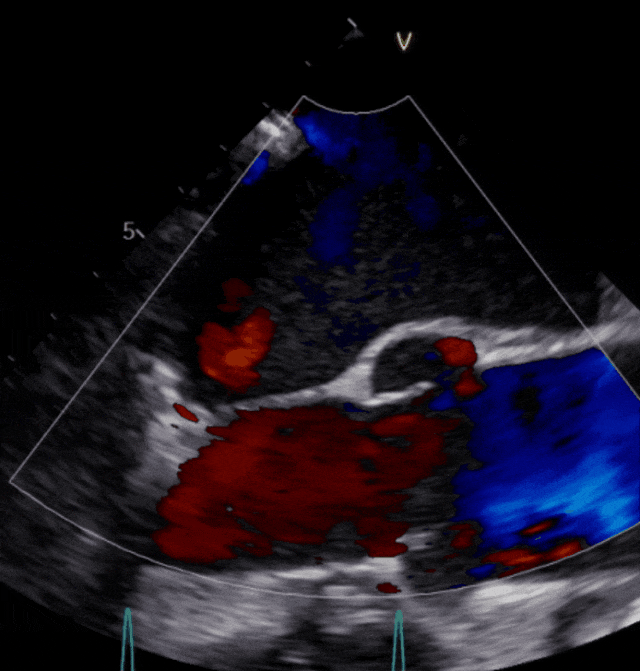

▲患者术后超声影像

手术经股静脉置管,房间隔穿刺并置入导引导管后,送入第一枚NTR,经过左房定位到达反流位置,准确捕获并夹合前、后瓣反流严重部位,原本重度的二尖瓣反流降低为中度,决定植入第二枚NTR,最终反流降低至轻度,超声评估夹子夹合稳定、肺静脉逆流改善、平均跨瓣压差3.17mmHg,患者各项生理指标正常,手术顺利完成。